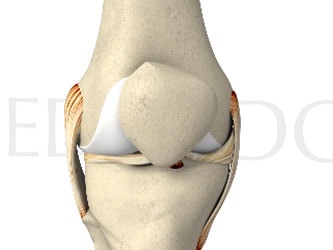

Chondral damage often accompanies ACL ruptures

Articular cartilage defects, although less common than meniscal pathology, were found in 30% of knees that recently underwent ACL reconstruction, according to a recent systematic review by Flanigan et al.4 Similarly, in an arthroscopic evaluation of 378 knees following acute ACL rupture, 163 patients (43%) had evidence of a concomitant full-thickness articular cartilage lesion.5

In another study, 146 of 663 (19.1%) patients showed evidence of at least one chondral lesion, with the majority (41%) localized to the medial femoral condyle.6 Among patients with a chondral lesion, 80% had a meniscal lesion and the primary ACL rupture in the same compartment. Moreover, the odds of having a serious chondral lesion (grade III/IV) were 2.7 times higher at 2 to 5 years post-injury and 12.6 times higher at > 5 years.

A concomitant chondral lesion was present in 36% of ACL ruptures documented in a retrospective analysis of over 25,000 knee arthroscopies.7 A much smaller retrospective analysis of 1,000 knee arthroscopies found an associated ACL rupture in 26% of chondral defects.8